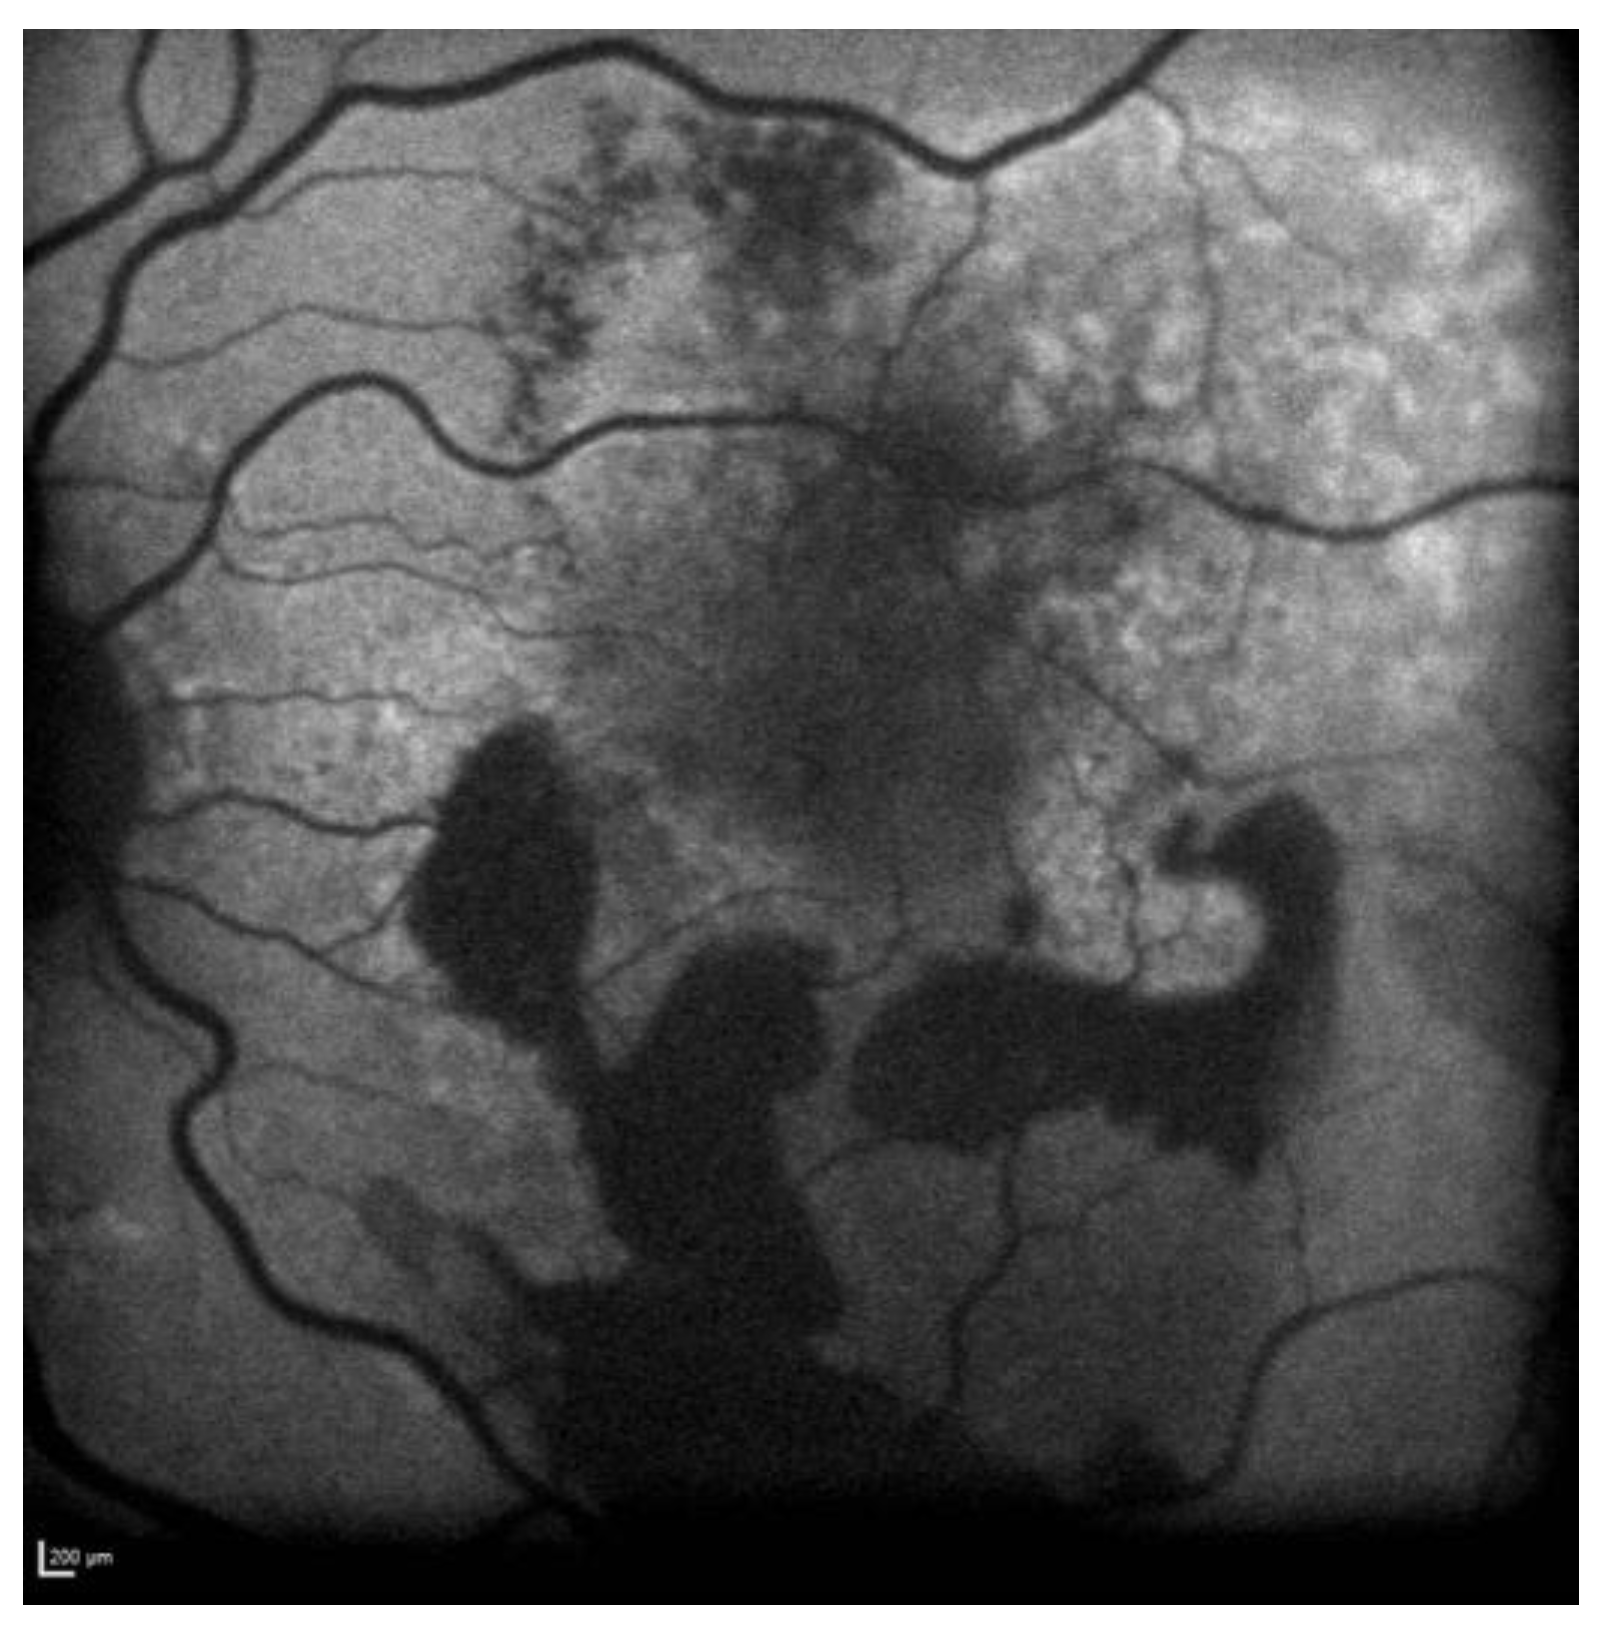

Fundus examination revealed a right greyish peripapillary lesion and macular drusen in the left eye. FAF was also performed, showing a right peripapillary hypoautofluorescent area (Figure 11).

Figure 11.

Case 7. Heidelberg Spectralis blue autofluorescence shows a peripapillary hypoautofluorescent lesion in the right eye.

The OCT scan demonstrated a type 1 MNV with PED and BALAD in the right eye. The ceiling of the BALAD presented hyper-reflective foci. The EZ zone was attenuated at the floor (Figure 12).

Figure 12.

Case 7. Heidelberg Spectralis optical coherence tomography shows a peripapillary type 1 MNV with subretinal fluid and BALAD in the right eye.

The OCTA scan confirmed the presence of the right peripapillary MNV (Figure 13).

Figure 13.

Case 7. Heidelberg Spectralis optical coherence tomography angiography shows a peripapillary subretinal neovascular membrane in the right eye.

These features were shown to be partially responsive to the treatment. The BVCA was stable over the treatment period.